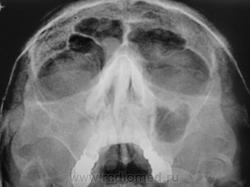

Больше похоже на кисту. Четкий округлый контур с характерным месторасположением. Хотя может и не так все просто)

да,  похоже на кисту, но справа снижена пневматизация верхнечел.пазухи за счет умеренного отека, я бы кисту слева под вопросом написала и направила на контроль

---------------------------------------------------------------------------------------------------------------------------------------------------------------------------------+1: как вариант,  можно предположить, что киста одонтогенного происхождения.

Второй случай. уровень слева,субтотальное затенение справа.киста правой половины лобной.....